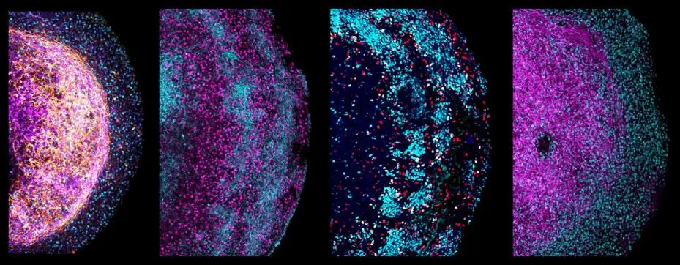

△ 成熟的大脑类器官(扩增2-3个月后成熟)中指示标志物的代表性免疫荧光图像。

△ 四张不同人类胎儿大脑器官的放大图像。不同的神经标记被染色,描绘了它们的细胞异质性和结构。